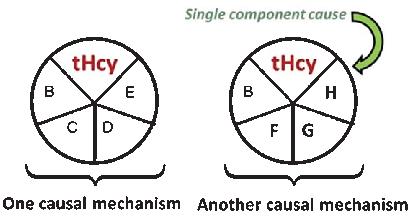

A causal model illustrates how elevated plasma homocysteine may contribute to dementia through multiple pathways, interacting with other risk factors such as age, hypercholesterolemia, and genetic predisposition. No single factor is sufficient alone; rather, combinations of component causes drive disease.

Homocysteine and Dementia: An International Consensus Statement.